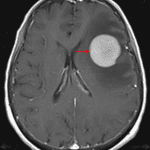

MRI

- T1 hypointense, T2 isointense mass with a rim of relative T1 signal hyperintensity and T2 signal hypointensity in the left frontal lobe measuring 3.4 x 3.3 x 3.2 cm with finger-like enhancing projections and a satellite enhancing lesion more superiorly in the left frontal lobe

- Homogeneous, diffuse corresponding enhancement and restricted diffusion

- No associated susceptibility artifact

- Surrounding vasogenic edema and corresponding mass effect resulting in local sulcal effacement, crowding of the left lateral ventricle, and left-to-right midline shift measuring 4 mm

- No downward herniation or hydrocephalus